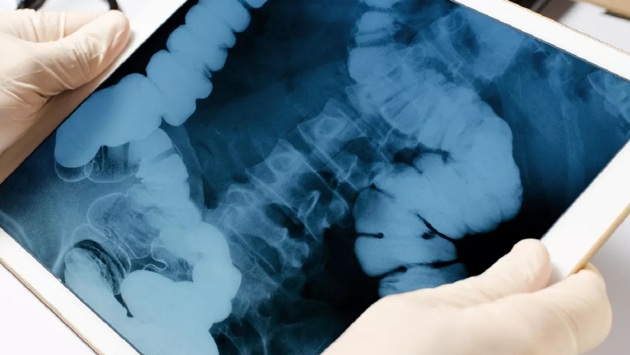

Колоректальный рак является одним из самых распространенных видов рака в мире, занимающий 3-е место по частоте выявления и 2-е место по количеству смертей среди злокачественных новообразований. При этом среди злокачественных опухолей желудочно-кишечного тракта этот вид рака занимает первое место.

По словам врача-онколога, заведующего ЦАОП Калачевской ЦРБ Кирилла Агапова, коварство этого вида рака заключается в том, что он разевается медленно и не дает о себе знать на начальных стадиях.

Заподозрить наличие опухоли можно при появлении крови в кале, хронических болей в животе, дискомфорте после еды, вздутии, нестабильном стуле и болезненной дефекации.

Агапов отметил, предупредить развитие колоректального рака легче, чем вылечить его. Основной группой риска онколог назвал людей, ведущих сидячий образ жизни.

Также среди основных факторов риска – неправильное питание, наследственность, хронические болезни кишечника, запоры, избыточный вес, возраст старше 50 лет.

Агапов рекомендовал для профилактики болезни больше двигаться и правильно питаться. Важно регулярно проходить скрининг, подчеркнул врач.